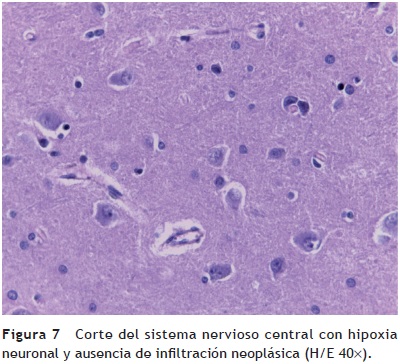

El cerebro tuvo un peso ligeramente disminuido con respecto al esperado, de 1150 g vs 1275 g, y presentó congestión importante de los vasos subaracnoideos visto por la convexidad y por la base. En los cortes seriados se observó discreta dilatación del sistema ventricular. Los cortes histológicos mostraron hipoxia neuronal (fig. 7). Se evaluaron numerosos cortes para confirmar la ausencia de blastos, tanto en los vasos subaracnoideos como en los vasos parenquimatosos. En este momento no había actividad neoplásica a nivel de sistema nervioso central ni en otro sitio.